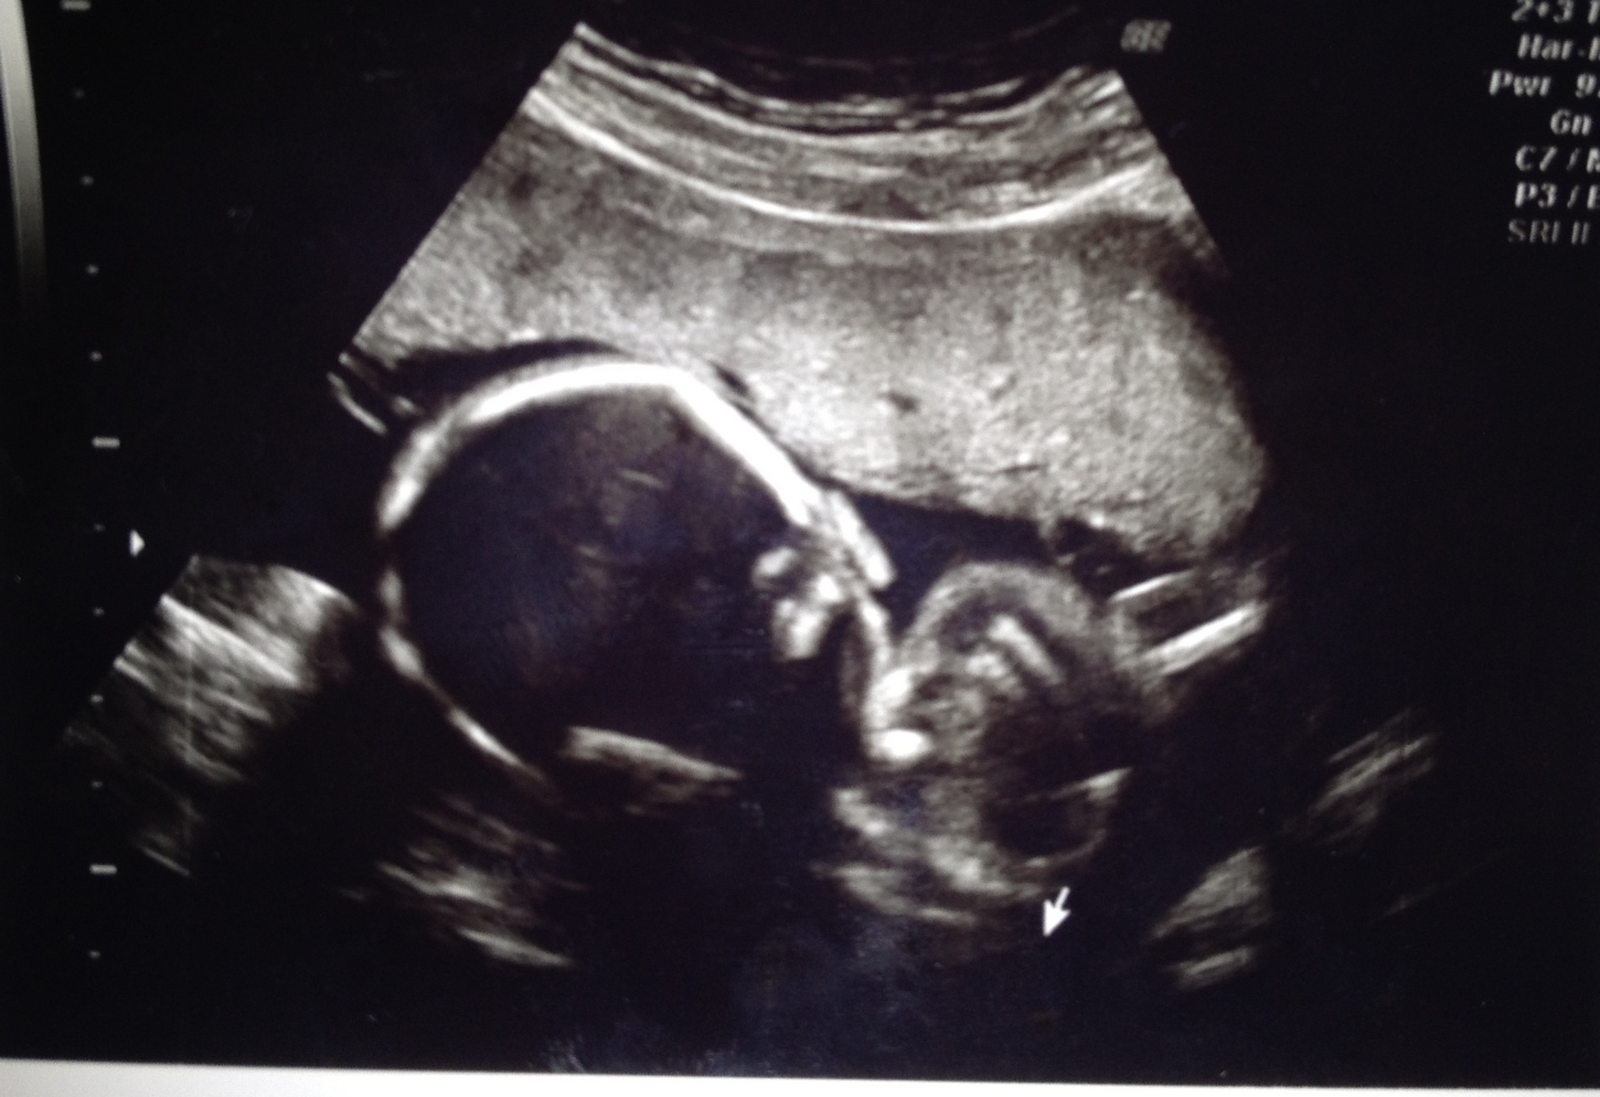

Rakenneultrassa käytiin kun viikkoja oli kasassa 21+1 (27.7.) Mua niin jännitti, etten saanut edellistä yötä kunnolla nukuttua..Aamulla kuitenkin pääsin kerrankin ylös nopeesti sängystä (huolimatta valvomisesta ;) ) ja lähettiin viemään Akselia hoitoon, kun ultra- aika oli jo klo 9. Miehen kanssa päästiin siis molemmat kurkkimaan pikkuista ja hänellä oli kaikki hyvin. Vastasi viikkoja ja painoarvio oli 436g. Niin ihana pienin. Nähtiin 4D kuvana kun "Hippu" imeskeli peukaloa ja muutenkin jumppaili. Voi sitä onnea. Saatiin myös veikkaus sukupuolesta, mutta tepä saatte sen tietää vasta sitten pikkuisen synnyttyä, jos en sitä vahingossa jossain lipsauta :)

Näin epäselvä kuva saatiin rakenneultrasta mukaan.. Jos tarkkaan osaat katsoa näet pikkuisen korvan :)